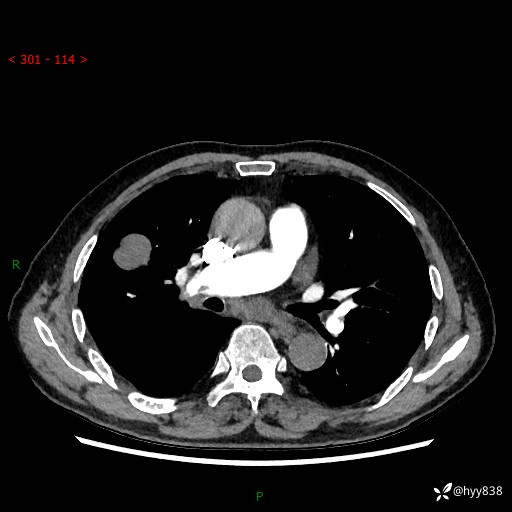

69岁/男,间断咳嗽伴气促、下肢水肿。临床拟诊肺栓,偶发肺均质强化结节--结果公布

【患者信息】:69岁/男

【主诉】:间断咳嗽伴气促、下肢水肿2周

【现病史及既往史】:患者2周来无明显诱因出现咳嗽,咳少量白痰,不易咳出,伴有气促,呈间断发作,症状与活动费力相关,以夜间为甚,不能平躺入睡,偶有憋醒,无胸闷胸痛、无发热、无头晕、头痛等不适,伴有双下肢中度水肿,就诊于当地县人民医院门诊,完善相关检查提示:左下肢深静脉血栓形成,未予以特殊处理,今患者为求进一步诊治来我院就诊,拟“心衰”收入我科。 起病以来,患者精神、饮食、睡眠可,大小便如常,体力明显下降,体重未见明显减轻。

【检查】:胸部CT增强